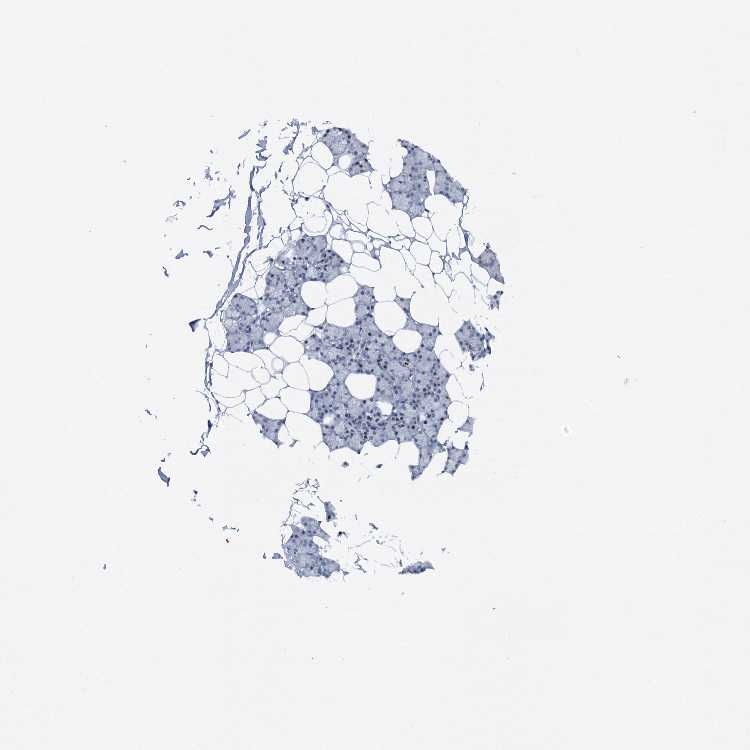

SALIVARY GLAND - Antibody stainingi

Antibody staining in the annotated cell types in the current human tissue is reported as not detected, low, medium, or high, based on conventional immunohistochemistry profiling in selected tissues. This score is based on the combination of the staining intensity and fraction of stained cells.

Each image is clickable and will lead to virtual microscopy that enables deeper exploration of all samples and also displays staining intensity scores, fraction scores and subcellular localization as well as patient and tissue information for each sample.

Antibody HPA039792

Glandular cells Low